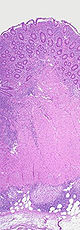

At the time of colonoscopy, biopsies of the colon are often taken in order to confirm the diagnosis. There are certain characteristic features of the pathology seen that point toward Crohn's disease. Crohn's disease shows a transmural pattern of inflammation, meaning that the inflammation may span the entire depth of the intestinal wall. Grossly, ulceration is an outcome seen in highly active disease. There is usually an abrupt transition between unaffected tissue and the ulcer. Under a microscope, biopsies of the affected colon may show mucosal inflammation. This inflammation is characterized by focal infiltration of neutrophils, a type of inflammatory cell, into the epithelium. This typically occurs in the area overlying lymphoid aggregates. These neutrophils, along with mononuclear cells, may infiltrate into the crypts leading to inflammation (crypititis) or abscess (crypt abscess). Granulomas, aggregates of macrophage derivatives known as giant cells, are found in 50% of cases and are most specific for Crohn's disease. The granulomas of Crohn's disease do not show "caseation", a cheese-like appearance on microscopic examination that is characteristic of granulomas associated with infections such as tuberculosis. Biopsies may also show chronic mucosal damage as evidenced by blunting of the intestinal villi, atypical branching of the crypts, and change in the tissue type ( metaplasia). One example of such metaplasia, Paneth cell metaplasia, involves development of Paneth cells (typically found in the small intestine) in other parts of the gastrointestinal system.